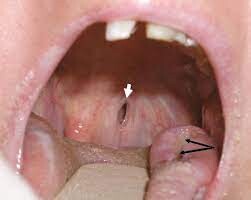

Vasculitis and Oral Health

Vasculitis can affect all parts of the body and the mouth is no exception. Large, persistent and excruciatingly painful mouth ulcers are sometimes a characteristic of active Wegener’s Granulomatosis as is severe toothache that moves around the mouth, especially in the upper jaw.